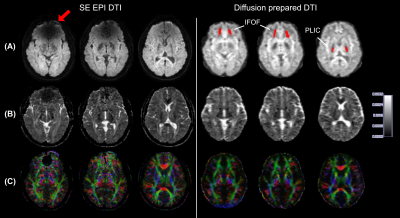

Figure 2. SE-EPI and diffusion-prepared DTI axial images acquired at 3.0 T in a participant wearing metallic dental braces. A, raw diffusion-weighted images, B, calculated ADC maps, and, C, fractional anisotropy map color coded by V1 orientation (standard red, green, and blue convention). Susceptibility artifacts were observed on SE EPI images in regions close to brace (arrow). No obvious artifacts were seen on diffusion-prepared DTI image. Regions of interest of IFOF and PLIC used in subsequent quantitative analysis are highlighted on diffusion-prepared DTI images with red.